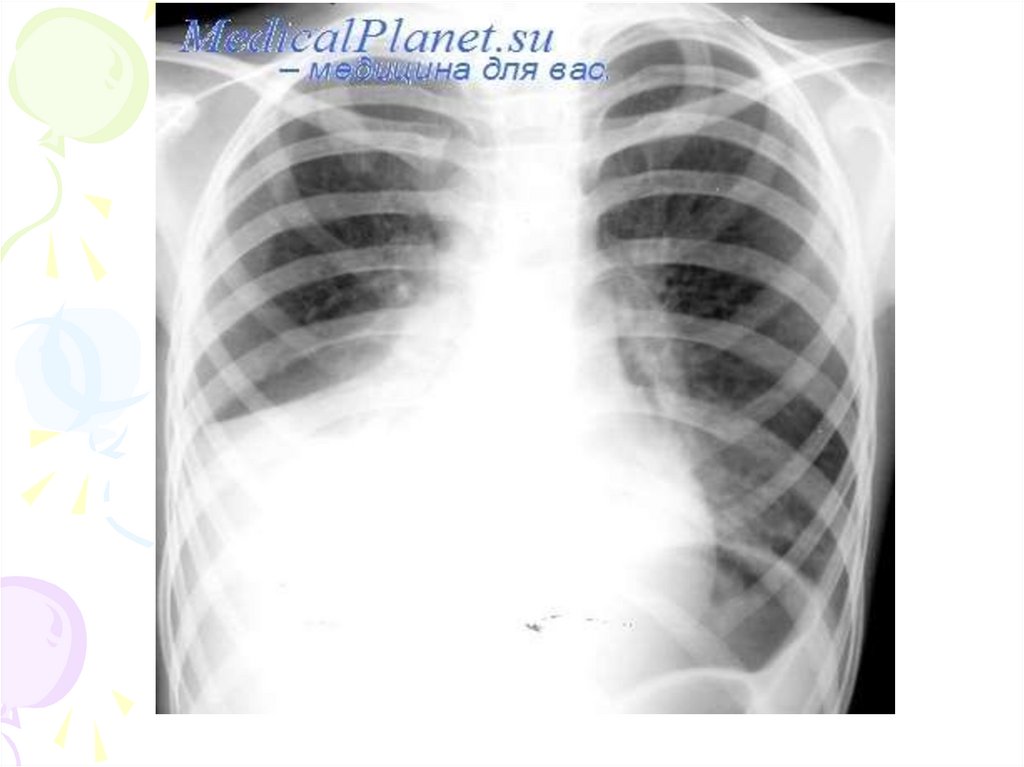

Сегментарная пневмония